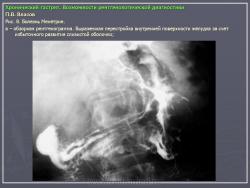

При гистологическом исследовании констатируется утрата высокодифференцированных специализированных клеточных элементов, перестройка по кишечному типу. Процесс атрофии, как правило, не затрагивает стромы. Атрофию можно рассматривать как разновидность тканевой дистрофии, где преобладают катаболические процессы над анаболическими. Еще в конце XIX века S. Fenwick описал распространенную атрофию слизистых оболочек всего желудочно-кишечного тракта при злокачественных опухолях иной локализации. Этот факт является свидетельством зависимости состояния слизистой оболочки желудка от протекающих в организме общих метаболических процессов. При гастрите часто наблюдается очаговая атрофия слизистой. Кроме того, при так называемых гипертрофических формах гастрита (в качестве примера может служить полипозный гастрит) обычно наблюдается дисплазия клеточных элементов с потерей дифференцировки специализированных клеток с заменой их низкодифференцированным эпителием покровного типа. С внедрением в клиническую практику гибких гастроскопов получил широкое распространение диагноз гипертрофического гастрита. Термин “гипертрофический”, введеный гастроскопистами, легко был принят рентгенологами, поскольку они часто наблюдали утолщенные складки слизистой оболочки желудка. Между тем патоморфологи, основываясь на гистологической картине, придерживались иного деления гастритов, в терминологии морфологов практически отсутствует понятие гипертрофического гастрита. Американские исследователи E.B. Benedict и T.B. Mallory провели корреляцию гастроскопических данных с патоморфологическими и установили, что описываемому гастроскопистами поверхностностному гастриту патоморфологически соответствует острое экссудативное воспаление. Термином “атрофический гастрит” эндоскопистами и морфологами описывается одно и то же состояние. Используемый гастроскопистами термин “гипертрофический гастрит” в большинстве случаев соответствует чрезмерно выраженной физиологической инфильтрации лимфоцитарными и плазмоцитарными клетками. На основании этих и многих других исследований сформировалось вполне обоснованное убеждение в том, что термин “гипертрофический гастрит” неправомерен, так как он не отражает существа изменений в стенке желудка. В большинстве случаев при этом слизистая желудка либо имеет нормальное строение, либо имеется банальное экссудативноинфильтративное воспаление без выраженной склонности эпителия к пролиферации. Обнаруживаемое эндоскопистами и рентгенологами утолщение складок слизистой, неровность внутренней по верхности желудка в виде булыжной мостовой в большинстве случаев являются выражением не равномерности скопления экссудата в строме слизистой оболочки и подслизистого слоя. Морфологическую основу этого феномена составляет неравномерный отек соединительной ткани, разделенной в виде каркаса на более или менее ограниченные ячейки. На рис. 1 показана рентгенологическая картина банального гастрита с перестройкой внутреннего рельефа желудка за счет отека слизистой оболочки и подслизистого слоя соединительной ткани.

Макроморфологические данные свидетельствуют о том, что любой воспалительный процесс в слизистой желудка изменяет внутреннюю поверхность желудка, она становится неровной за счет появления полипоидных и подушкообразных возвышений, вызванных неравномерным отеком и воспалительной инфильтрацией слизистой оболочки. На рентгенограммах подобные инфильтраты отображаются в виде дефектов наполнения с нечеткими, неровными очертаниями. Переходя на контуры желудка, подобные инфильтраты создают неровность малой и большой кривизны. Изменения обычно локализуются в антральном отделе, а при пангастрите распространяются практически на весь желудок (см. рис. 1).

Гастрит часто сопутствует язве желудка или двенадцатиперстной кишки, фактически он представляет собой один из компонентов язвенной болезни и никаких особенностей не представляет. Следует, правда, отметить, что при язвенной болезни чаще, чем при других формах, встречаются спастические реакции антрального отдела и эрозии. Одно из наблюдений сочетания язвенной болезни и гастрита представлено на рис. 4. В рентгенологическом изображении в желудке при всех формах гастрита обнаруживается гиперсекреция, которая выражается в большем или меньшем количестве жидкости и слизи натощак. Стенки желудка, при гастрите, сохраняют эластичность. Перистальтика обычно не изменена. Вместе с тем при гастрите нередко обнаруживается спазм антрального отдела желудка, который выражается укорочением или сужением препилорического отдела. Рельеф слизистой антрального отдела при этом перестраивается. При укорочении атрального отдела складки располагаются поперечно, антральный отдел приобретает вид гармошки. Такой гастрит называется ригидным антральным гастритом. Одно из наблюдений ригидного антрального гастрита приведено на рис. 5. Многочисленные экспериментальные и клинические исследования свидетельствуют о том, что антральный отдел желудка является своеобразной рефлексогенной зоной, выполняющей важную роль в секреторной и моторноэвакуаторной деятельности пищеварительного тракта. Известно также, что этот отдел четко реагирует на различные патологические процессы в других отделах желудка или отдаленных органах. Многие рентгенологи 30–40 х и 50 х годов прошлого века описывали спастические реакции антрального отдела в ответ на язву тела желудка. Известный французский рентгенолог R.Gutman еще в 1938 г. опубликовал работу, которую прямо назвал “Les deformations pseudoneoplastiques de l’antre dasns l’ulcere de la petite courbure” (“Псевдоопухолевая деформация антрального отдела при язве малой кривизны желудка”). Казалось бы, ясней некуда. Однако в отечественной литературе все подобные деформации антрального отдела в многочисленных публикациях 50–60 х годов XX века, на наш взгляд, ошибочно описывались под названием “ригидный антральный гастрит”. А то, что через 2–3 года у половины больных с подобными изменениями антрального отдела в этой области развивался рак, выдавалось за высокий индекс малигнизации данной формы гастрита. Следовательно, у значительной части больных под маской ригидного антрального гастрита развивается инфильтративный рак. Отрицательные данные гастроскопии и биопсии скорее говорят о пределах возможностей метода, чем об отсутствии рака.